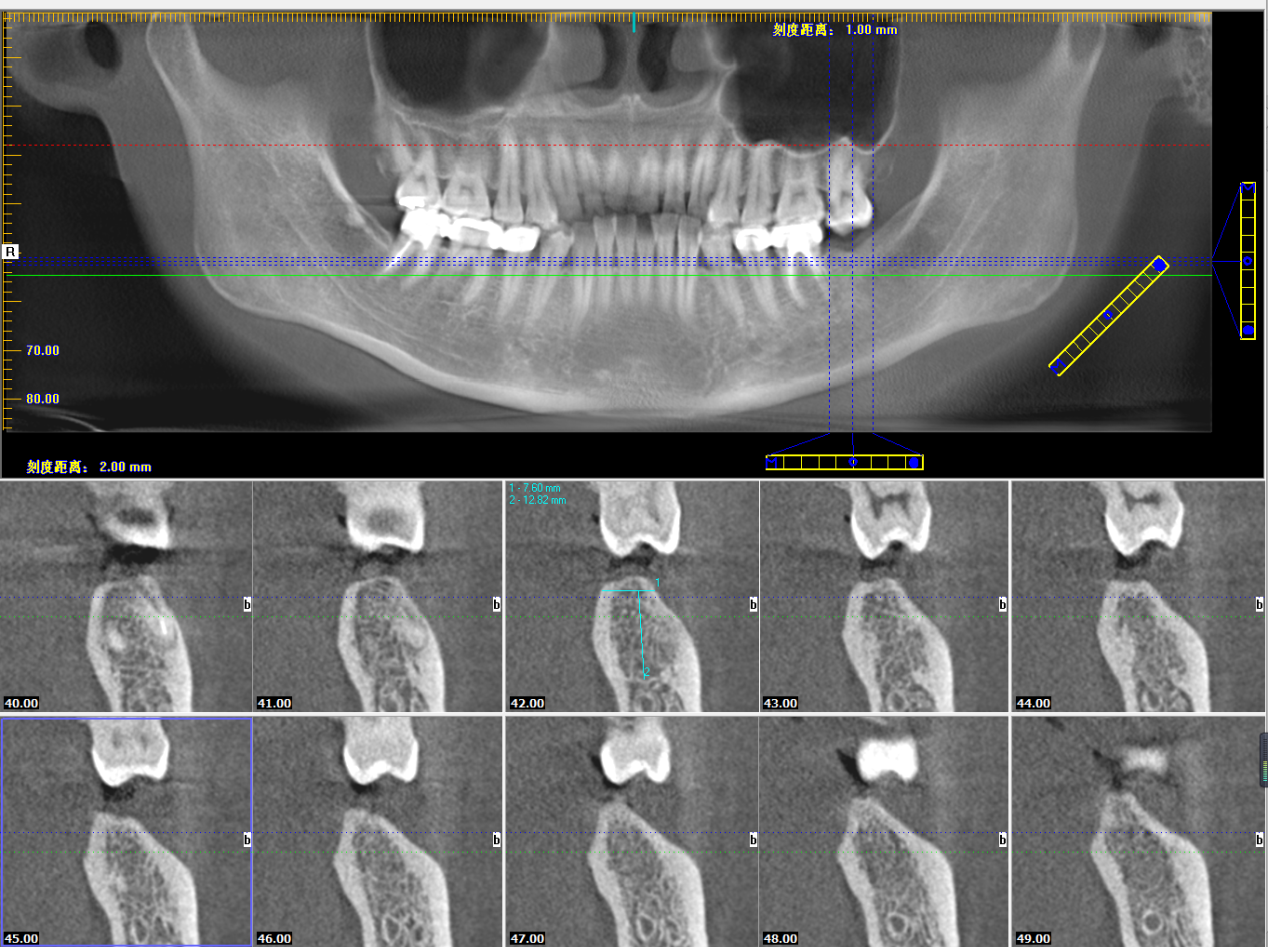

其实,对于医生来说,很多时候不能“眼见为实”,肉眼对口腔的观察,远没有CT来得直观、全面、精确,拍摄CT是为了更好的治疗。

本次种植直播患者,韩女士。34岁,左下侧第二磨牙蛀牙缺失,选择韩国OSSTEM种植体。

姚江武院长运用数字化精准种植牙技术,在短短7分钟内,就将种植体植入患者牙槽骨内,展现了高超的种植技术,实现种植过程快速舒适、精准安全、微创无痛的临床效果。